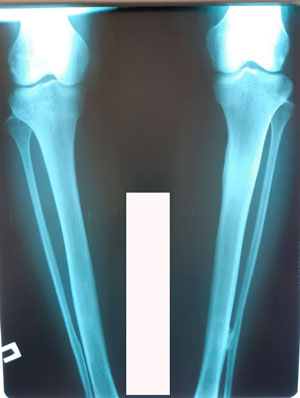

Исходник 32 года. Якутия

Дата операции - 05.02.2020г